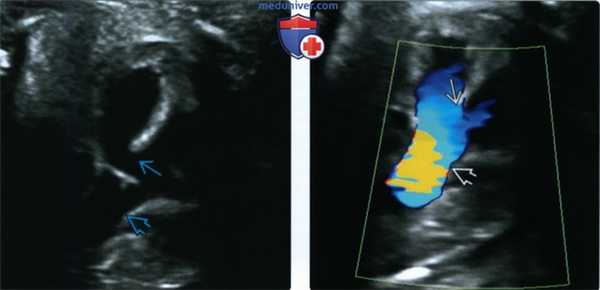

(Слева) Общий АВ-клапан «обхватывает» дефект в центральной части сердца, затрагивающий межпредсердную и межжелудочковую перегородки. Смешивание крови внутри сердца ведет к тому, что кровь в аорте и легочной артерии насыщена кислородом в равной степени.

(Справа) УЗИ. Визуализируются крупный ДМЖП и единственный клапан разделяющий две камеры сердца. Межпредсердная перегородка отсутствует. Желудочки имеют одинаковые размеры, поэтому дефект в данном случае, скорее всего, сбалансированный. (Слева) ЭхоКГ плода, четырехкамерный срез. В систолу видны сбалансированный АВСД, общий АВ-клапан а также непрерывный дефект межпредсердной и межжелудочковой перегородок. Характерная картина смещенных друг относительно друга клапанов отсутствует.

(Справа) ЦДК в диастолу. Кровь целиком заполняет АВСД. «Крест сердца» не визуализируется, происходит полное смешивание оксигенированной и неоксигенированной крови.